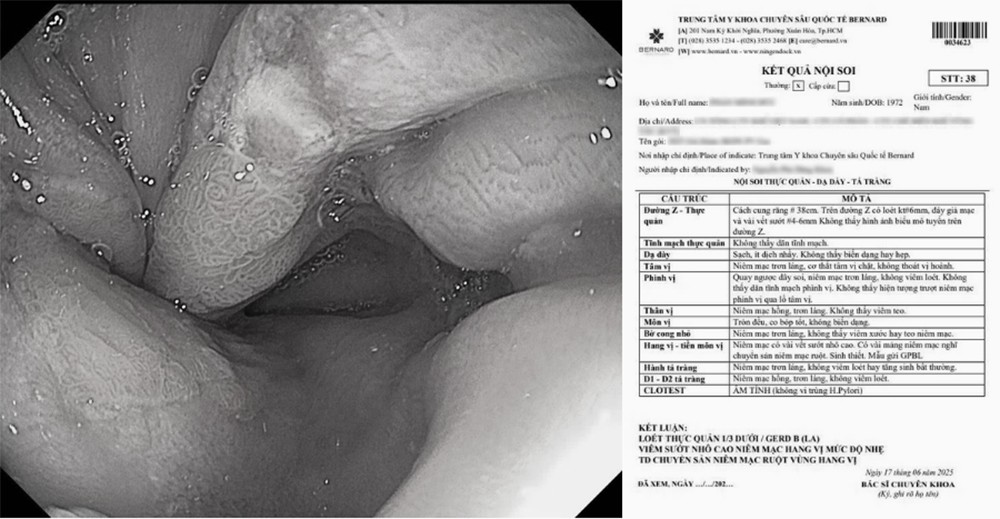

Một trường hợp người bệnh thừa cân, tăng mỡ cơ thể sau 2 năm, tiến triển thành GERD độ B và loét thực quản

Nội soi tiêu hóa giúp phát hiện sớm các tổn thương thực quản điển hình của GERD